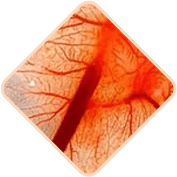

Gemorroyda kengaygan qon tomirlari shikastlanishi va yorilishi mumkin, bu qon ketish xavfini oshiradi. Qon ketishining og'irligi yengildan og'irgacha o'zgarishi mumkin, bu jarrohlik aralashuvini yoki hatto qon quyishni talab qiladi.

Surunkali gemorroy qon tomirlarida qon quyqalarining paydo bo'lishiga olib kelishi mumkin. Vaqt o'tishi bilan bu qon quyqalari boshqa ichki organlarning tomirlarini sindirib, to'sib qo'yishi mumkin, bu yesa qon tomirlari, o'pka emboliyasi va koronar tromboemboliyani keltirib chiqaradi.